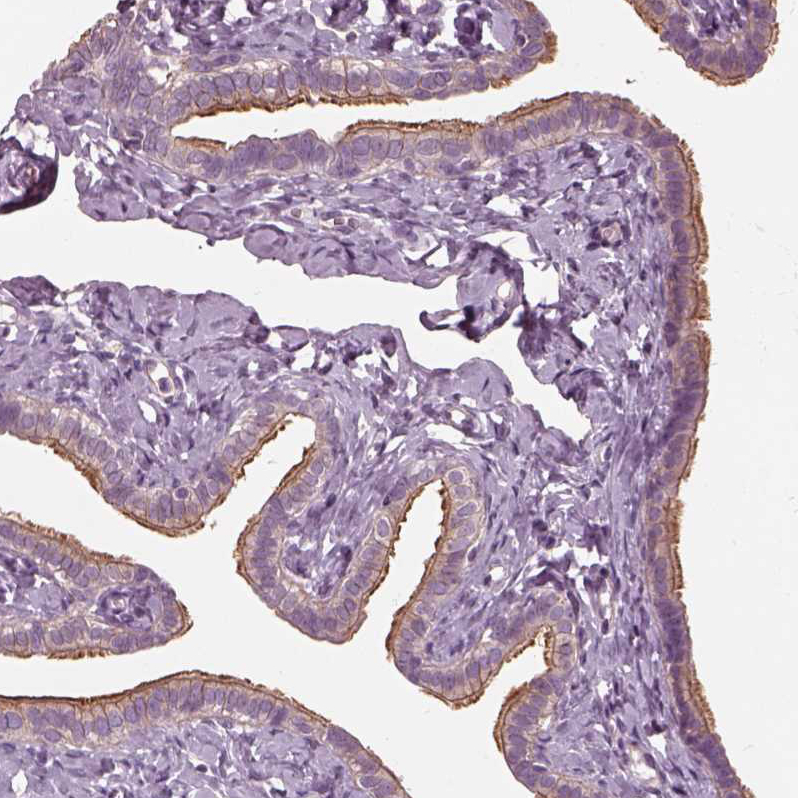

Immunohistochemical staining of human fallopian tube shows strong positivity in cilia in glandular cells.